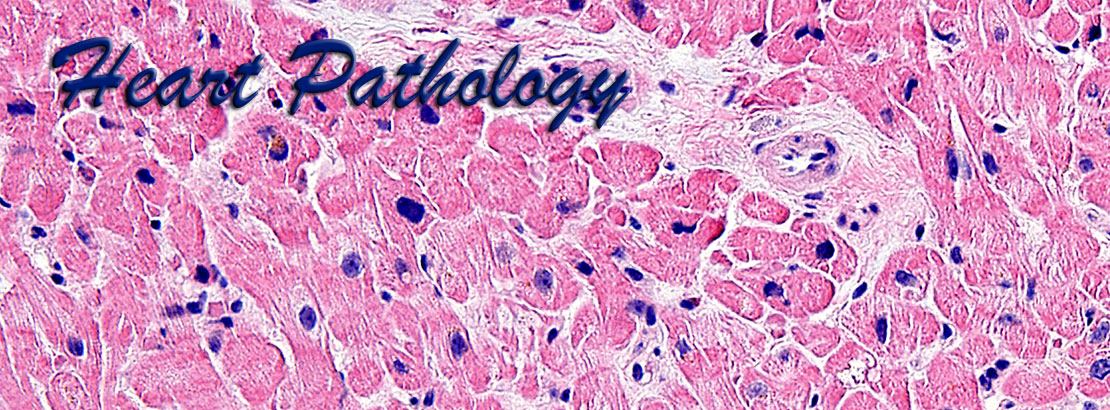

Cardiac pathology is an important area of pathology but is not comprehensively taught at many medical centers due to the paucity of cardiac specimens outside of the autopsy services. Our website uses high definition images obtained from gross pathology specimens and histological slides, both at a resolution of 1800x1350 pixels. Most images have been obtained using Olympus digital cameras.

The images presented here represent a wide variety of heart pathology cases, including acquired diseases, transplantation pathology, idiopathic diseases, tumor pathology, etc., and are accompanied by brief morphological descriptions. The histological images are shown at different optical magnifications and include conventional stains such as hematoxylin-eosin, PAS, trichrome stains, as well as immunohistochemical stains. Also included are some images from normal tissues and from positive and negative controls for the corresponding special stains.